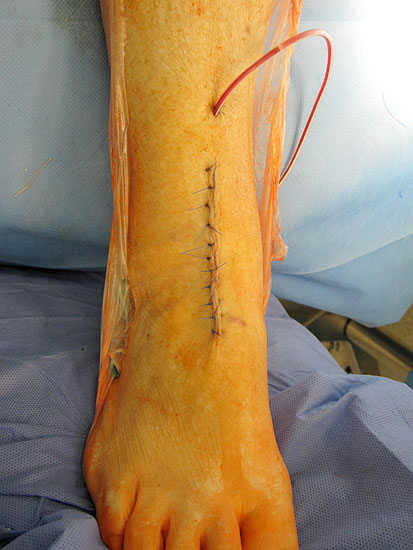

1. Wundheilungsstörung infolge einer hohen intraoperativen Druck- und Zugbelastung auf den periartikulären Weichteile; Lösung: dosierte Weichteilbehandlung durch die Hacken durch den Assistenten; aktive Erinnerungen während der Operation (Abb. 20 und 21)